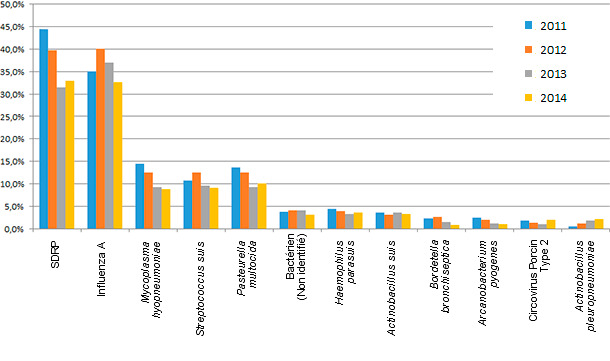

Figure 1 : Pourcentage de diagnostic d’agents étiologiques par rapport aux prélèvements envoyés. Source : ISU